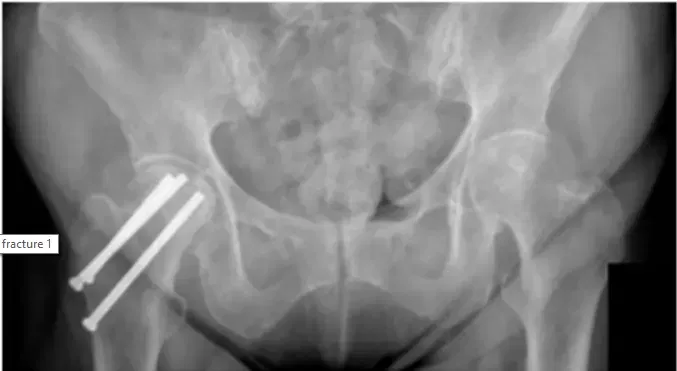

La patiente est une femme de 68 ans qui s’est plainte de douleurs à la hanche droite après avoir subi une intervention chirurgicale pour réparer une fracture antérieure de la hanche droite. Le patient a apporté des radiographies pour examen, comme indiqué ci-dessous,...